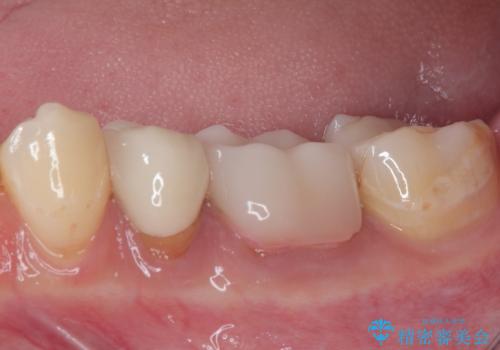

左下奥歯は詰め物と周辺の歯が欠けて、しみている状態でした。

部分的な詰め物ですと、再度破損リスクが高いため、高強度のセラミッククラウンにて補綴治療を行うこととしました。

セラミッククラウンを壊して再度根管治療を行い、その後セラミッククラウンを装着する方法か、外科的に歯根の先端を切除し、炎症の原因である細菌を取り除き治癒を図る方法とを提案し、極力クラウンを壊さずに治療を進めたいとの希望により、歯根端切除術を行うこととしました。